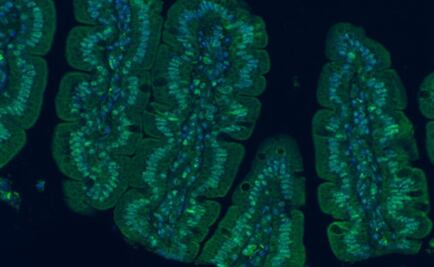

El proyecto MyNewGut muestra la influencia de la microbiota intestinal en el balance energético que regula el peso corporal y en la función cerebral

La microbiota ejerce importantes funciones relacionadas en el cuidado de la salud